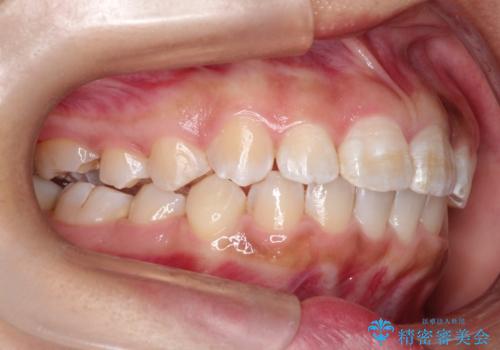

マウスピース矯正で前歯のガタツキを改善! ワイヤー矯正併用でかみ合わせもしっかり治します

- 前歯のガタツキが気になると来院されました。

マウスピース矯正治療を選択しました。

前歯のガタツキを改善する治療法として、マウスピース矯正が適していることが多いです。

マウスピース矯正は、金属製のブラケットやワイヤーを使用せずに、透明なマウスピースを装着して歯を移動させる方法です。そのため、目立たず、痛みも少ないです。

この症例では、奥歯のかみ合わせの改善を目的にワイヤー矯正を併用しました。奥歯のかみ合わせをより緊密にするため、また短期間に治療するためにはワイヤー矯正が適していることがあります。